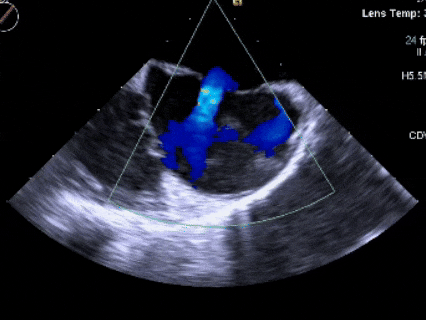

CDFI示:房水平左向右分流。上、下腔静脉回流入右房正常。冠状静脉窦未见扩张。

超声可见房间隔连续中断,彩色多普勒可见过隔血流

彩色多普勒血流成像显示无残余分流存在